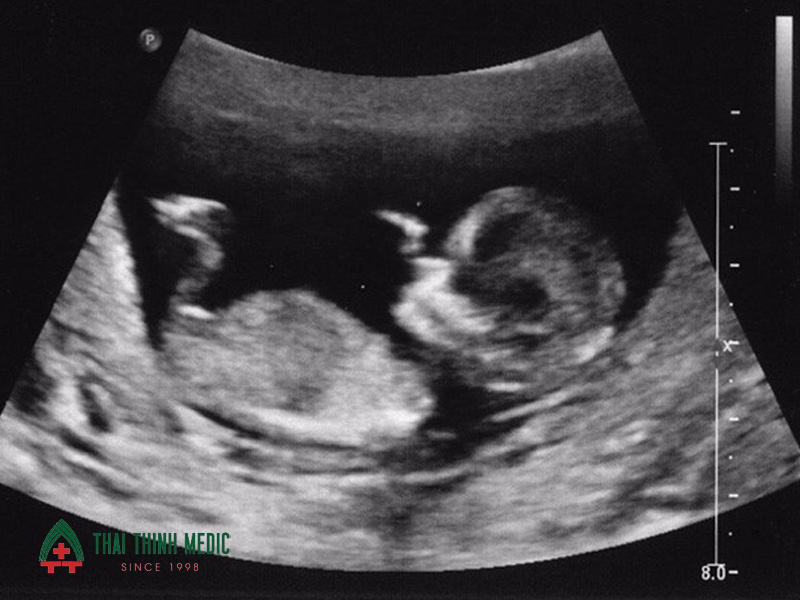

Đo chiều dài đầu mông

CRL (Crown-Rump Length – chiều dài đầu - mông) là chỉ số đo từ đỉnh đầu đến mông của thai nhi, là cơ sở quan trọng để đánh giá tuổi thai chính xác và dự kiến ngày sinh. Ở tuần 12, CRL thường dao động từ 45–84 mm tùy vào sự phát triển của từng thai nhi. Chỉ số này còn giúp bác sĩ so sánh sự phát triển của thai nhi so với mức chuẩn, phát hiện sớm các bất thường về tăng trưởng.